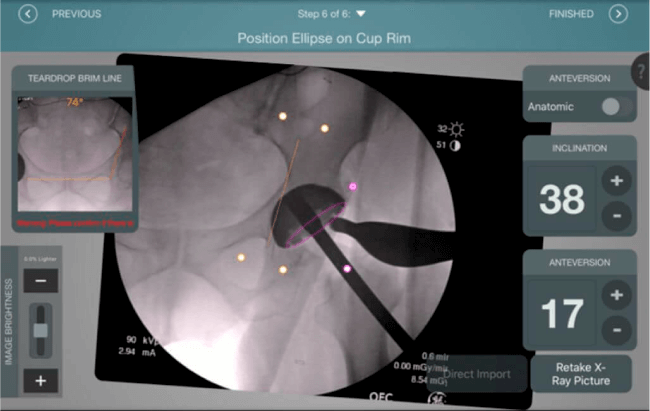

El sistema de navegación digital VELYS HIP NAVIGATION ™ para cirugía de cadera, es una tecnología innovadora y no invasiva diseñada para potencializar la toma de decisiones en tiempo real y basada en datos; aumentando la precisión y mejorando los resultados a corto, mediano y largo plazo para los pacientes.

Datos procesables en tiempo real para la toma de decisiones.

Mayor nivel de información intraoperatoria facilita la colocación correcta de los implantes:

Inclinación y anteversión de la copa acetabular para una correcta colocación del implante.

Verificación de la posición deseada del implante que potencialmente puede ayudar a reducir la probabilidad de dislocación protésica y aumentar la estabilidad de la articulación.